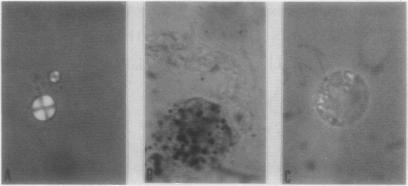

Experimental haemarthrosis produces mild inflammation associated with intracellular Maltese crosses.

Injection of autologous blood into rabbit joints induces an inflammatory reaction with Maltese cross-like birefringent spherulites. Similar microspherules seen in human joint fluids may be formed by lipids derived from breakdown of erythrocytes and other cells.